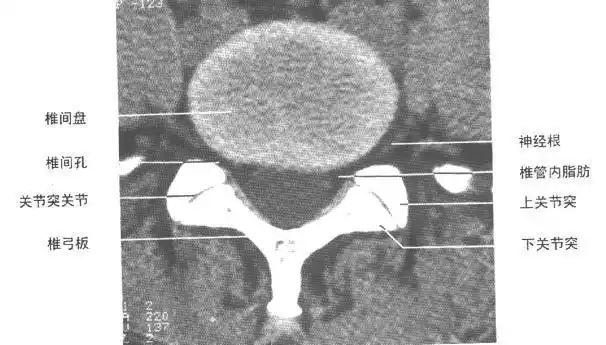

腰椎ct诊断ppt